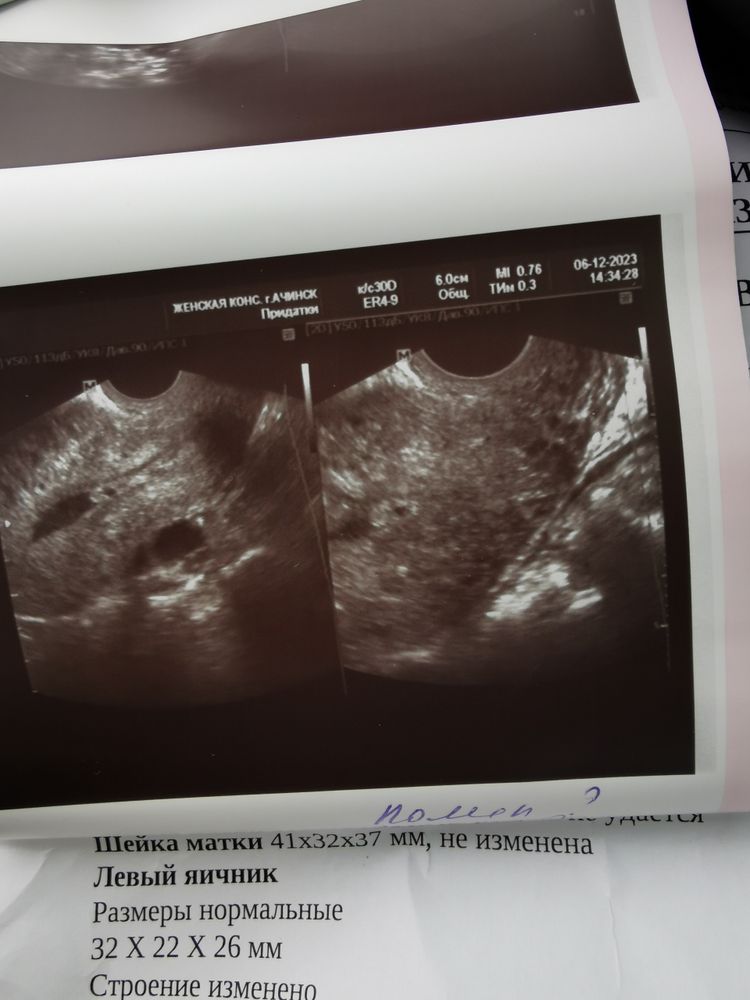

Сегодня, заканчивая 6 месяцев приёма Визанны, сделала ещё узи и там:

Эндометрий 12 мм!

Внутренний эндометриоз и полип , которых никогда не было!

И ещё якобы миома на другой стенке 9 мм, которой тоже никогда не было!

А ещё рубец на матке с 8х10 три месяца назад стал 19х22 сегодня!

Фолликулярнвя киста уменьшилась и стала 16х16.